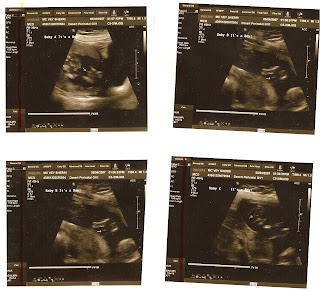

We have an office visit on 4/20/07 to check on the babies before the cerclage. Babies are great, growing well.